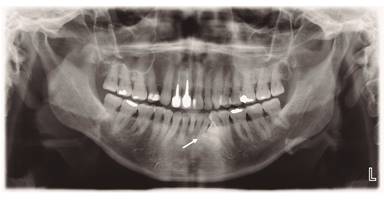

El presente estudio es parte del proyecto de investigación PRI_ODO 16/05 de la Facultad de Odontología de la Universidad de Chile y cuenta con autorización del Comité de Ética de la Facultad. La probando III.1, se examinó por primera vez a causa de una consulta de operatoria. Se solicitó una radiografía panorámica en la cual se observó la presencia de un odontoma compuesto entre raíces de pieza 26 y 27(Fig. 1). Al realizar la anamnesis y preguntar por antecedentes familiares de patología intestinal, la paciente menciona que dos tíos fallecieron de cáncer de colon (sujetos II.5 y II.9), un primo operado con colectomía profiláctica por poliposis intestinal (sujeto III.5). Dos tías con antecedentes de poliposis colónica (II.1 y II.2), y una de ellas con historia de cáncer gástrico (la sujeto II.1), tratada y con buena evolución. Se contactan a familiares de la probando. Cuatro integrantes de la familia de la probando, aceptaron participar en el estudio. Al hacer la genealogía familiar, se omiten en ella los integrantes de los que no se obtuvo información relacionada a PAF. (Fig. 2)

Dentro de las AD más comunes, se encuentra: la ausencia congénita de dientes, impactación, hipercementosis, dientes supernumerarios, odontomas y morfología dentaria anormal7. En la familia chilena estudiada, la probando (III.1) presentó un odontoma compuesto; el sujeto III.5 anomalías de morfología de las piezas 7 y 10; y presencia de calcificaciones intracamerales en molares de paciente III.1 y III.5.